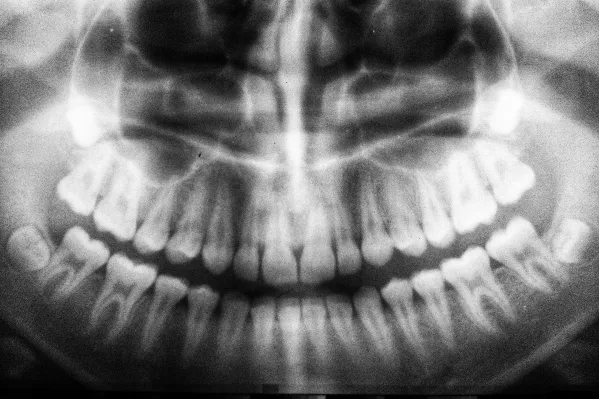

Dorosły człowiek ma zazwyczaj od 28 do 32 zębów stałych. Ta liczba może się różnić w zależności od obecności zębów mądrości, które są ostatnimi zębami pojawiającymi się w jamie ustnej. W typowym pełnym uzębieniu stałym znajduje się 8 siekaczy, 4 kły, 8 zębów przedtrzonowych oraz 12 zębów trzonowych. Zęby mądrości mogą się nie rozwijać u niektórych osób lub wymagać usunięcia z powodu braku miejsca w szczęce.

Standardowa liczba zębów u dorosłych wynosi od 28 do 32. Zwykle, w pełnym uzębieniu, zęby mądrości są uwzględniane w tej liczbie, co może wpływać na całkowity wynik. U niektórych osób zęby mądrości mogą nie rozwijać się wcale, co skutkuje posiadaniem jedynie 28 zębów. W przypadku, gdy zęby mądrości są obecne, ich liczba może wzrosnąć do 32.

W liczbie zębów u dorosłych mogą występować znaczące indywidualne różnice. Genetyka odgrywa kluczową rolę w tym, ile zębów ma dana osoba. Niektórzy ludzie mogą mieć więcej zębów z powodu obecności zębów mądrości, podczas gdy inni mogą ich nie mieć wcale. Dodatkowo, stan zdrowia jamy ustnej, taki jak choroby dziąseł czy wcześniejsze ekstrakcje, również wpływa na ostateczną liczbę zębów. W rezultacie, liczba zębów może się wahać od 28 do 32, a czasami nawet mniej, jeśli występują poważne problemy zdrowotne.